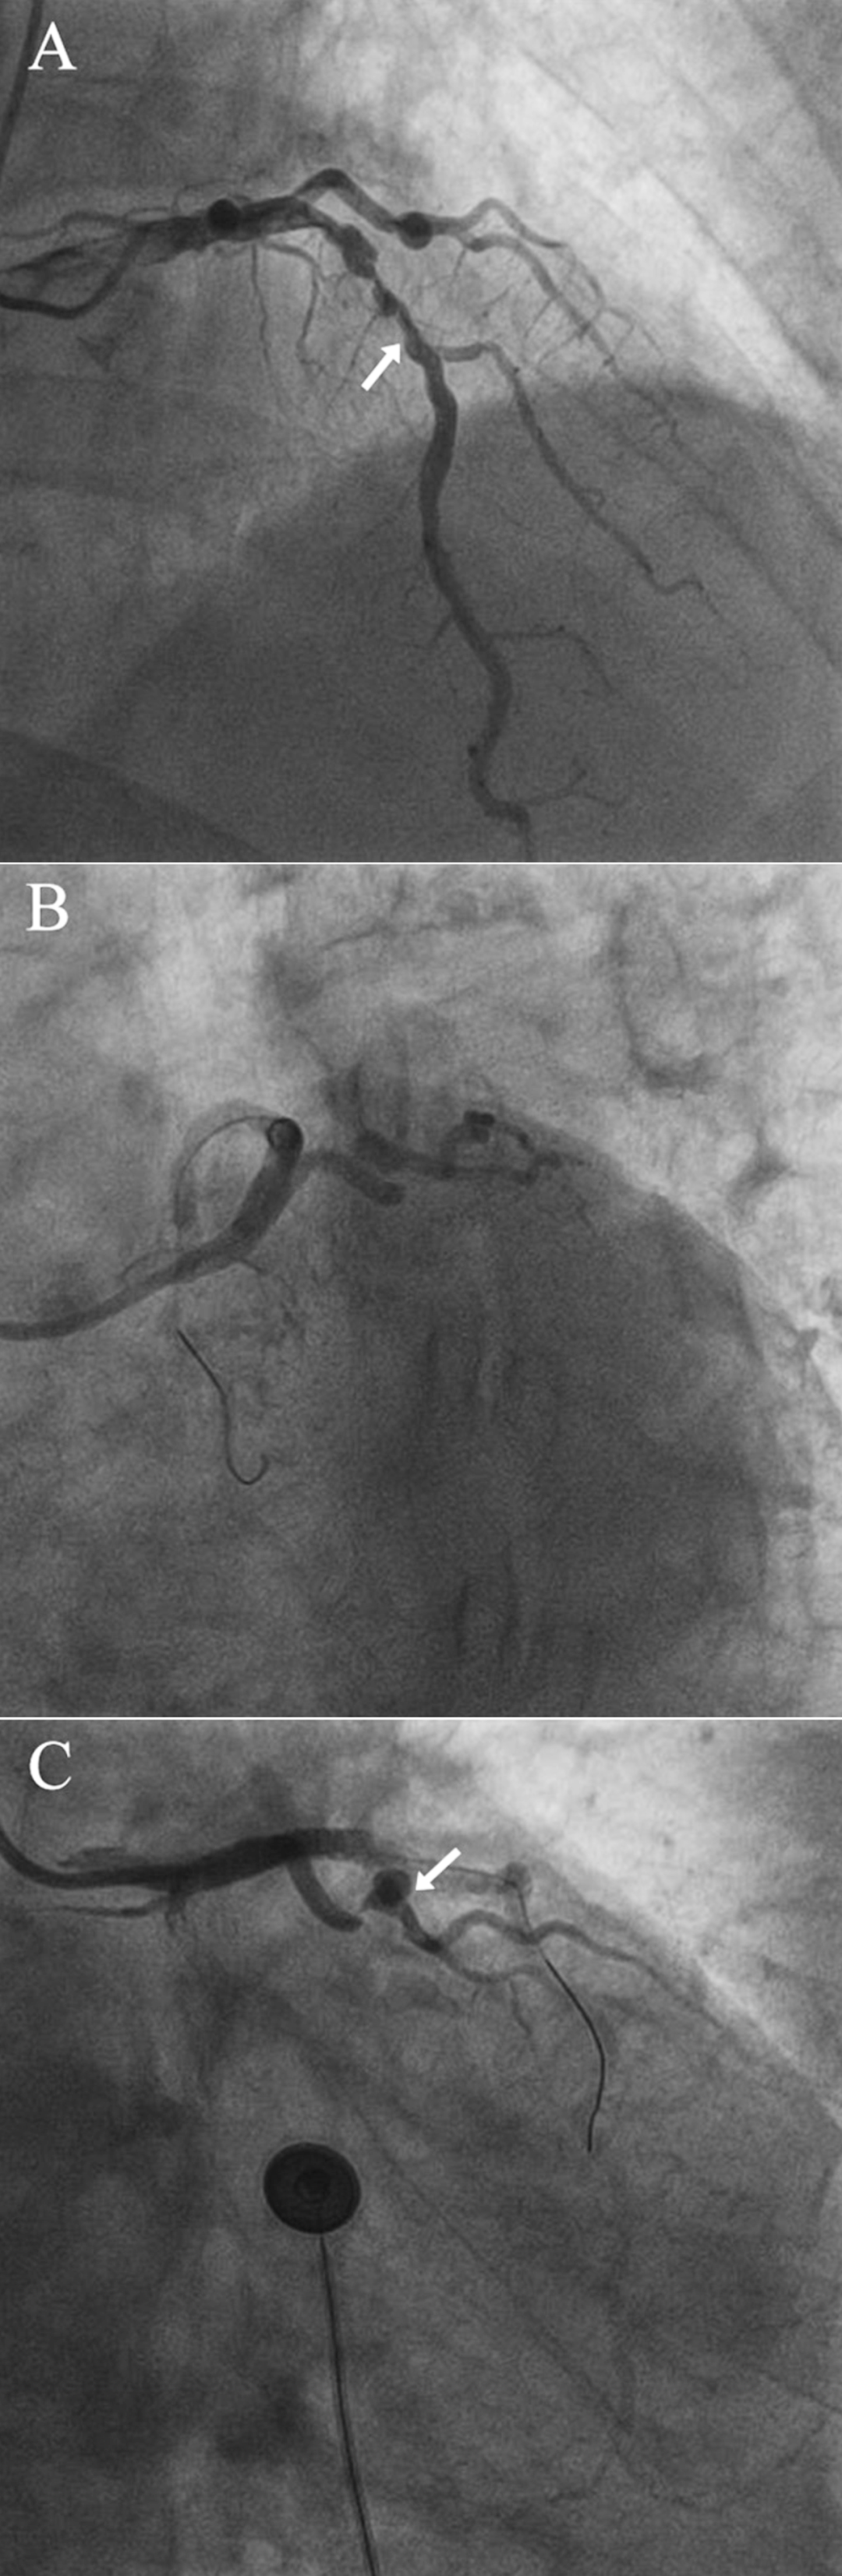

冠脉造影显示(图 1A-C):

左回旋支(LCX)完全闭塞

左前降支(LAD)严重狭窄

高位对角支近端重度狭窄伴环状扭曲

冠脉远端可见多发微小冠脉-心室瘘

图1冠状动脉造影结果

(A)箭头指向左前降支(B)严重狭窄且迂曲的冠状动脉(C)箭头指向环状血管结构。